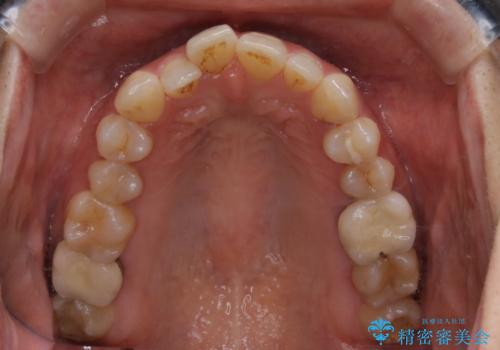

- 前歯のがたつきと反対咬合を主訴に来院されました。

インビザライン・クリンチェック(歯のシミュレーション)を行い、

インビザラインライトで治せる範囲であることを確認し治療を開始することになりました。

今回はクリンチェックを作成したのちに、枚数が少なくても可能であることが判明したためインビザラインライトでの治療を行いました。

最初はインビザラインモデレートパッケージの予定で契約をされていたので、金額も10万円以上安くなり仕上がりも満足頂きました。